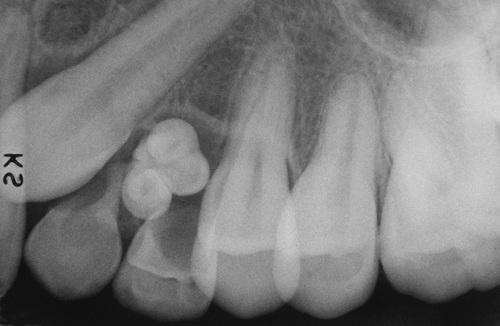

odontoma

A small cluster of toothlike structures is preventing the eruption of the maxillary canine.

compound odontoma

Multiple toothlets preventing the eruption of the mandibular cuspid.